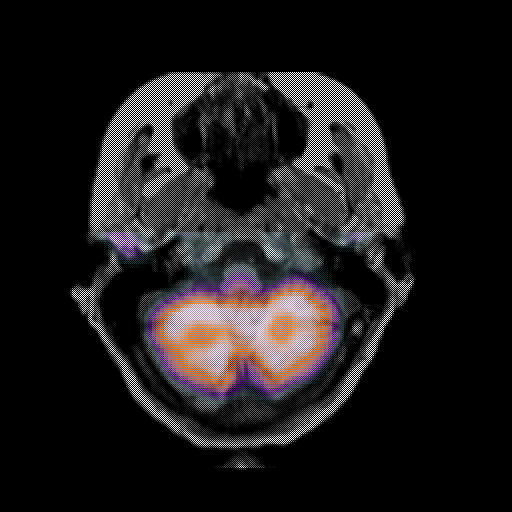

overlay: Slice 10

Slice 10

MRCBFCBF with

T1PDT2T1PDT2